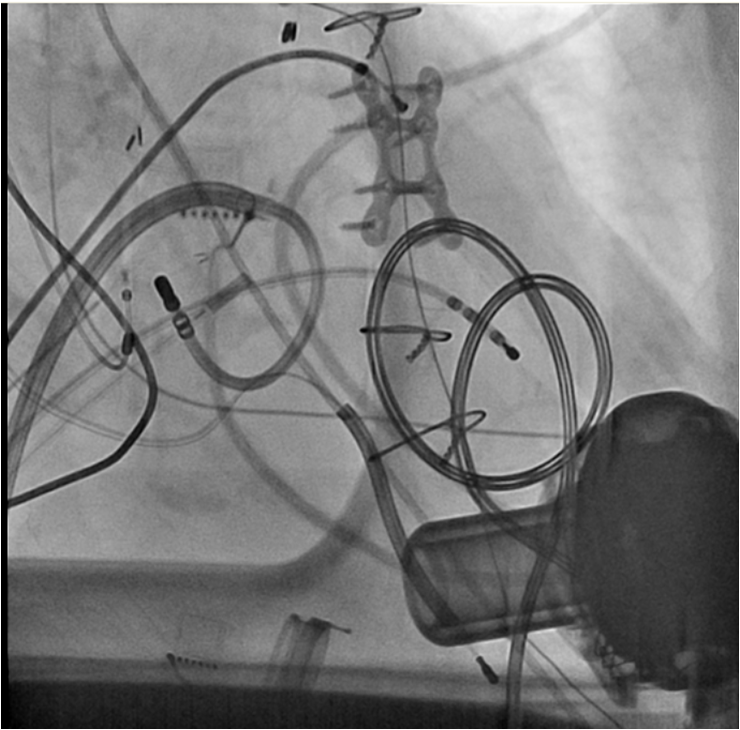

Where's Waldo Comes to EP

Here's the picture (yes, there's a heart in there somewhere):

Now, name the technologies seen.

-Wes